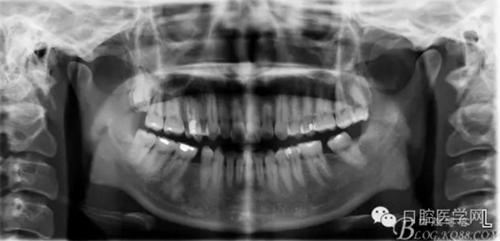

正畸醫(yī)生都想把患者做到“理想頜”,而臨床工作中卻很難如愿;這個(gè)患者到診時(shí),口內(nèi)已經(jīng)有兩顆恒牙缺失;

37,45缺失后,鄰牙近中移動(dòng)占據(jù)了部分牙位;患者要求減少治療費(fèi)用,不做種植修復(fù),那怎么協(xié)調(diào)右側(cè)的咬合關(guān)系?